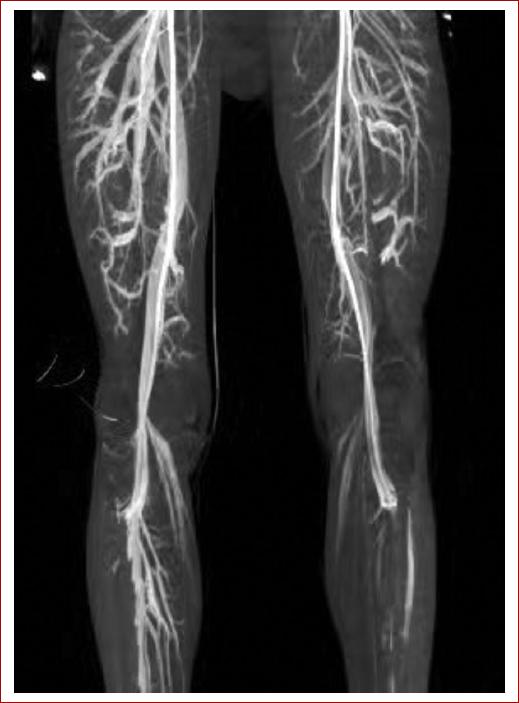

Posterior a la cirugía el paciente cursa con adecuada evolución clínica, comienza bipedestación sin síntomas de isquemia y deambulación asistida, por lo que al segundo día posquirúrgico es dado de alta. Actualmente el paciente cuenta con 3 meses libre de sintomatología, a la exploración ambas piernas presentan flujos trifásicos distales con índice tobillo-brazo izquierdo de 0.9 y derecho de 1.1, se mantendrá en seguimiento anual (Fig. 4).